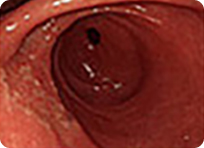

조기위암

조기 위암

위 내시경 검사는 인체 내부를 관찰할 수 있는 내시경 기계를 이용하여 식도와 위를 통해 십이지장의 중간 부분까지 들어가서 식도염, 식도암, 위염, 위궤양, 위암, 십이지장 궤양 등 위, 식도, 십이지장의 질병을 가장 정확히 진단할 수 있는 검사입니다.

특히 최근에는 내시경 기계의 발달로 수 mm크기의 작은 미소 위암이나 식도염도 조기에 진단이 가능합니다.